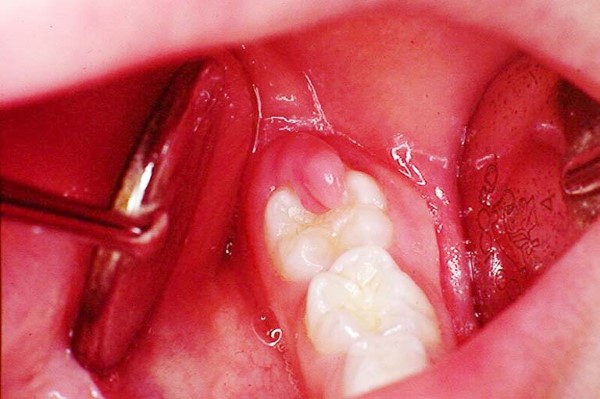

Theo bác sĩ nha khoa, phẫu thuật cắt lợi trùm là một thủ thuật tương đối đơn giản và nhanh chóng. Mục đích chính là loại bỏ mô lợi dư thừa che phủ bề mặt răng, thường gặp nhất là răng khôn. Việc này giúp răng mọc lên dễ dàng hơn, đồng thời ngăn ngừa tình trạng sưng viêm, giảm nguy cơ tích tụ thức ăn và vi khuẩn, từ đó phòng tránh các biến chứng nghiêm trọng như viêm lợi trùm có mủ. Thủ thuật này bao gồm việc bóc tách, giải phẫu liên kết hàm với mô lợi, lật vạt lợi lên và cắt bỏ phần lợi thừa bám trên thân răng, làm lộ thân răng, giúp răng trông dài hơn hoặc loại bỏ phần lợi bị viêm nhiễm.

- Răng khôn mọc thẳng nhưng bị lợi trùm: Việc cắt bỏ lớp lợi sẽ giúp răng khôn phát triển bình thường và giảm nguy cơ ảnh hưởng đến các răng khác.

- Răng khôn mọc lệch hoặc ngầm: Lợi trùm cản trở sự mọc lên của răng khôn mọc lệch hoặc ngầm. Trong trường hợp này, bác sĩ có thể chỉ định cắt lợi trùm kết hợp với nhổ răng khôn để phòng ngừa biến chứng do răng mọc sai hướng gây ra về lâu dài.